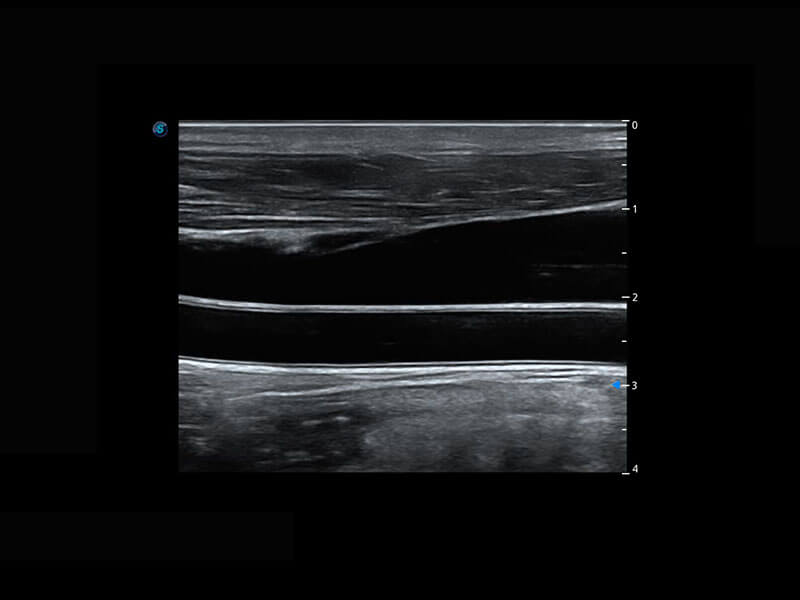

P60搭载宽频带线阵探头、宽景成像、弹性成像技术,为您提供乳腺应用方案。P60支持高频相控阵探头、线阵探头、腹部高频探头、腹部微凸探头等,丰富的探头群搭载敏感的彩色血流成像,适用于新生儿多种脏器检测要求,满足新生儿筛查需求。

新生儿脊髓圆锥

新生儿心脏